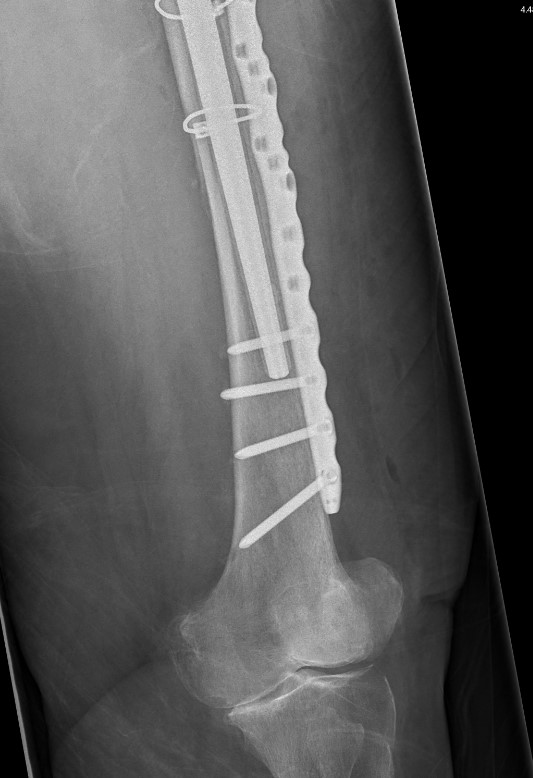

Type C: Fracture distal to tip of stem

Management

ORIF Locking cable plate +/- cortical strut allograft

- overlap femoral implant

- to distal femur